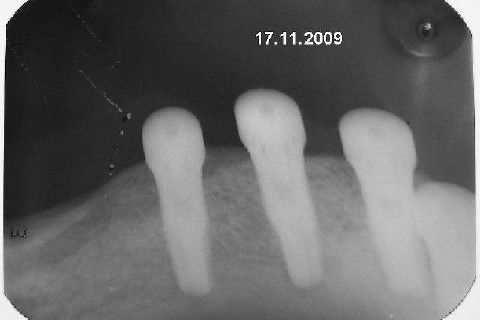

Apesar da boa adaptação e estética satisfatória, a principal queixa da paciente era a instabilidade da prótese inferior, como sempre ocorre nestes casos...atrofia do rebordo alveolar e perda da função mastigatória.